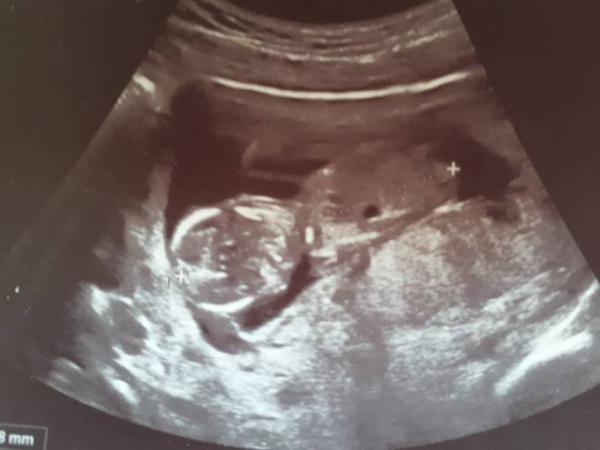

Man sieht doch nicht immer alles auf den Bildern, gerade wenn die Zwerge sich bewegen. Ich habe auch ein Bild ohne Beine von meinem Baby, da hat der Arzt extra gesagt, dass es selbstverständlich Beine hat, die er aber halt gerade nicht einfangen konnte. Ist von 11+0

Bild zu